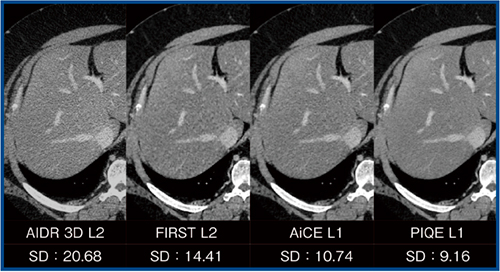

図4は,前述の超高体重患者における,異なる再構法による画像比較である。PIQEはSD:9.16と最もノイズ抑制効果が高く,分解能を維持したままノイズが抑制されていることがわかる。

図4 異なる再構成法による画像比較